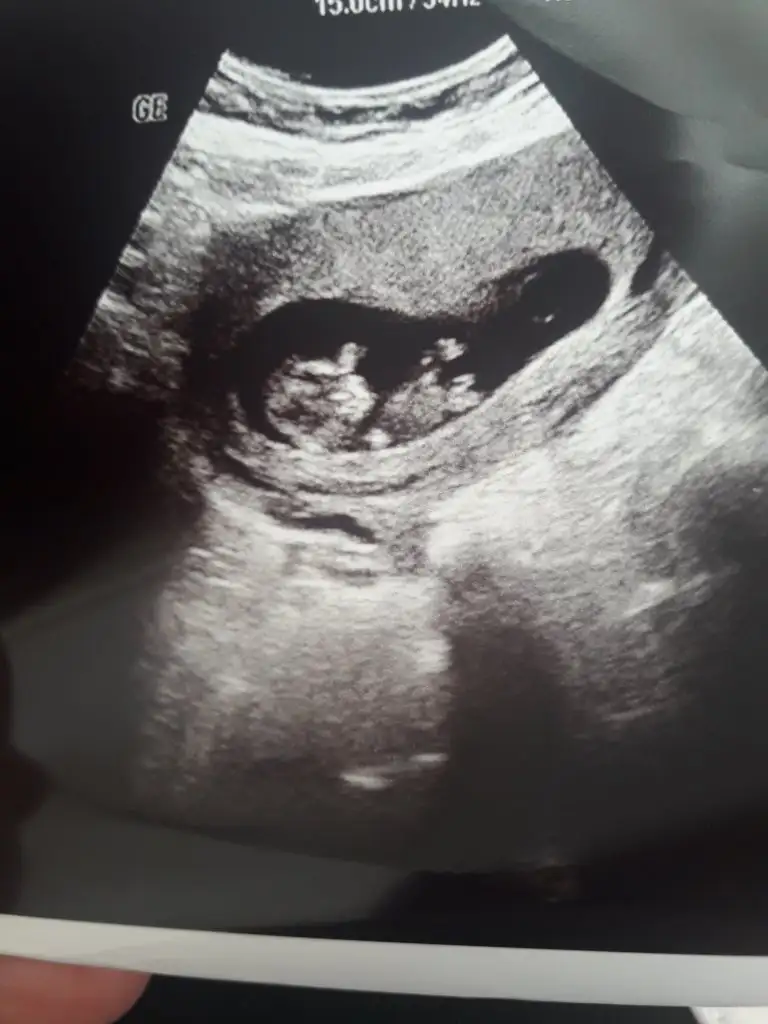

Sanki sanki diyerek kız gibi gibi tekrar USG paylasinBana da yorum yapabilir misiniz @İkra meyra. Ultrason cihazı biraz kötüydü ama 11 haftalık

Kaç haftalık büyük sanki USG 11 12 13 haftalar olmalı sanki sanki kız gibi tekrar USG paylasinBana da tahminde bulunabilir misiniz acaba